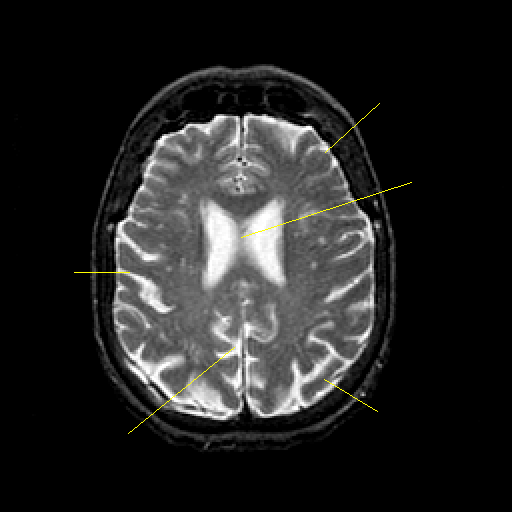

T2-weighted structural MR: Slice 35

Slice 35

Pointers

Labeled